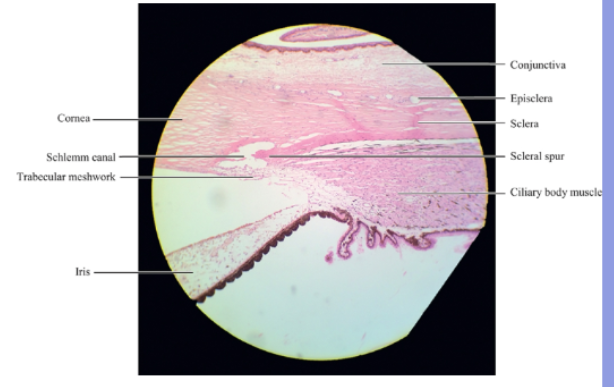

sclera

thick dense connective tissue layer that is continuous with corneal stroma at the limbus.

collagen fibrils are arranged into lamellae but are more irregular than the corneal lamellae

the irregular running of lamellae coupled with the irregular spacing between scleral components induce light scattering which makes the sclera opaque

scleral spur

its a region of circularly orientaated collagen bundles that extends from the inner aspect of the sclera

At the posterior edge its fibres blend with the scleralfibres and in cross section looks like a spur

limbus

located t corneascleral junction that encircles the periphery or cornea.

episclera

episclera is a vascularised connective tissue that lies infront of the sclera

episclera is joined to the tenon capsle by stands of connective tissue

conjunctiva

divided into 3 sections

the bulbar conjunctiva which covers the sclera

the palpebral conjunctiva which lines the eyelids

the conjunctival fornix which is the cul de sac connecting the other 2.

located at the intersection between cornea and sclera

the external and internal scleral sulci associated with this transtion are clearly visible in cross sections through the limbus